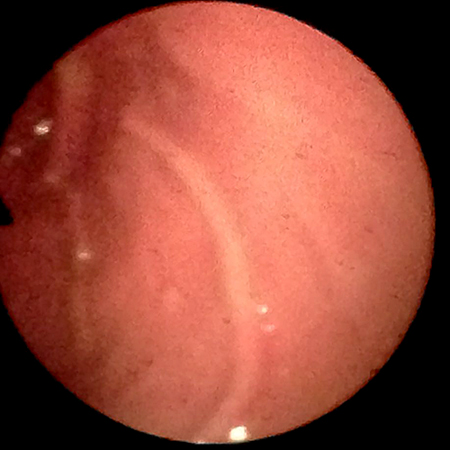

Endoskopie

Darmuntersuchungen

normale Schleimhaut